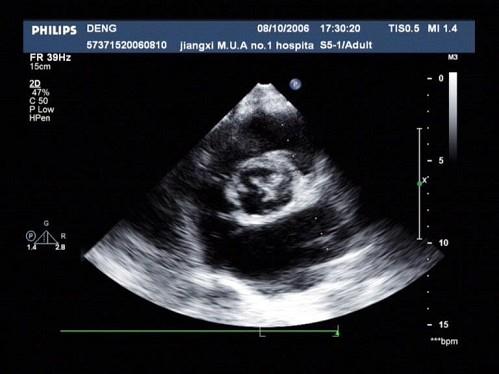

问题 患者,男,50岁,发热半月余,全身不适,乏力,食欲不振。根据超声心动图,最可能的诊断是?(?)

选项 A.风湿性心脏病 B.感染性心内膜炎 C.老年退行改变 D.主动脉瓣狭窄 E.冠心

答案 B